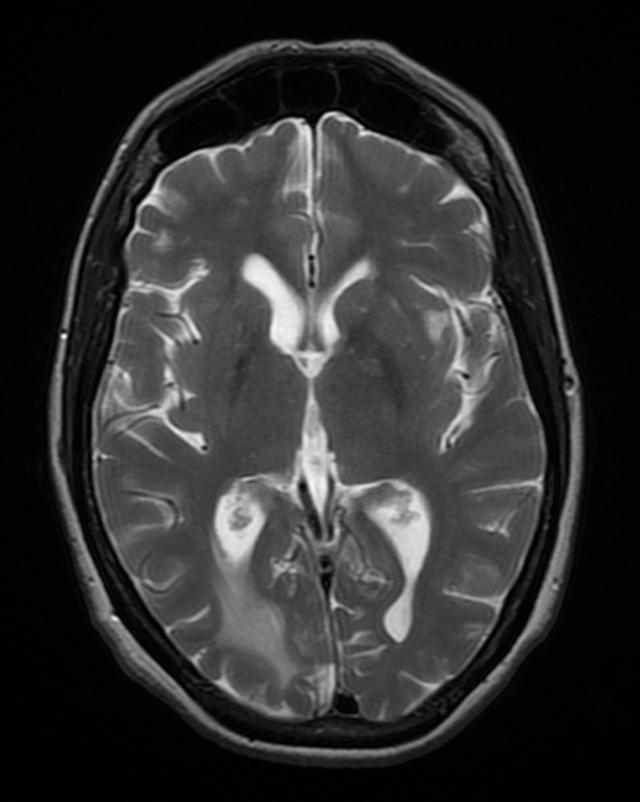

Brain toxoplasmosis

Right occipital lobe toxoplasmosis in a patient with AIDS

Source: Wikimedia commons, Jmarchn

https://upload.wikimedia.org/wikipedia/commons/f/f3/BrainToxoplasmosis_MRI_4_11.png

- T. gondii encephalitis presents as fever, headache, confusion, seizure, and focal motor findings with ring-enhancing lesions [Fig 4]. Patients with encephalitis may present with a non-focal, nonspecific illness, headache, and psychiatric symptoms.

- Imaging for TE is contrast-enhanced CT or MRI that shows multiple ring-enhancing lesions with surrounding edema in the gray matter of the cortex or basal ganglia.

- Occasionally, TE can present as a single lesion.

- Multifocal lesions on contrast-enhanced brain CT or MRI, especially in the basal ganglia.

- Typical radiographic appearance + therapeutic response = presumed diagnosis.